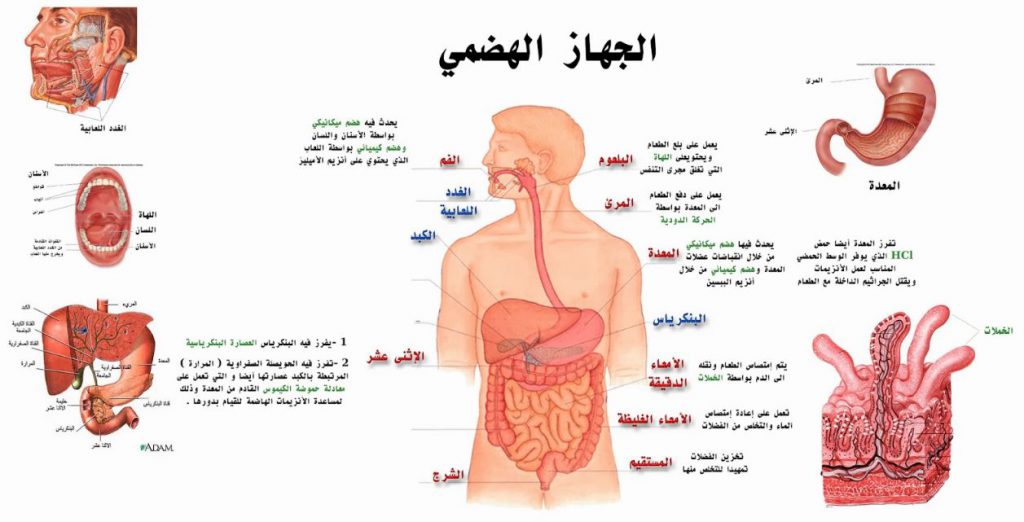

الجهاز الهضمي هو أحد أهم الأجهزة في جسم الإنسان، حيث يقوم بتحويل الطعام الذي نتناوله إلى مواد يمكن للجسم امتصاصها واستخدامها لإنتاج الطاقة وبناء الخلايا والحفاظ على وظائف الجسم المختلفة. يبدأ هذا النظام المعقد من الفم، حيث يتم مضغ الطعام وخلطه باللعاب، مرورًا بالمريء، .المعدة، والأمعاء، وصولاً إلى الإخراج

يتكون الجهاز الهضمي من مجموعة من الأعضاء التي تعمل بتناغم ودقة، تشمل الفم، البلعوم، المريء، المعدة، الأمعاء الدقيقة والغليظة، بالإضافة إلى أعضاء مساعدة مثل الكبد والبنكرياس. يلعب هذا الجهاز دورًا أساسيًا ليس فقط في هضم الطعام، بل أيضًا في التخلص من الفضلات، .وتنظيم مستويات السكر، وإنتاج إنزيمات ومواد ضرورية لصحة الجسم

الأعضاء الأساسية في الجهاز الهضمي

الفم

.الوصف: هو بداية الجهاز الهضمي، حيث يدخل الطعام إلى الجسم

:الوظائف

.الهضم الميكانيكي: يتم تقطيع الطعام إلى أجزاء صغيرة بواسطة الأسنان، مما يسهل بلعه

الهضم الكيميائي: يتم خلط الطعام باللعاب الذي يحتوي على إنزيم الأميلاز، الذي يبدأ في هضم .الكربوهيدرات

.اللسان: يساعد في تحريك الطعام داخل الفم وتشكيل بلعة جاهزة للبلع

.المخرجات: ينتج عن هذه العملية بلعة طعام يمكن نقلها إلى المريء

المريء

.الوصف: أنبوب عضلي يمتد من البلعوم إلى المعدة

الوظيفة

نقل الطعام من الفم إلى المعدة باستخدام حركة عضلية تُعرف بـ “الحركة الدودية”، وهي عبارة عن انقباضات وانبساطات متناسقة لجدران المريء

يحتوي على صمام (العضلة العاصرة السفلى) يمنع رجوع الطعام والأحماض من المعدة إلى- .المريء

.مدة المرور: تستغرق البلعة من 5 إلى 10 ثوانٍ للوصول إلى المعدة

المعدة

.الوصف: كيس عضلي مجوف يقع في الجزء العلوي من البطن.

الوظائف

.الهضم الميكانيكي: خلط الطعام بواسطة تقلصات جدران المعدة

الهضم الكيميائي: إفراز حمض الهيدروكلوريك

.(HCl) لقتل الجراثيم وتوفير بيئة مناسبة لإنزيم البيب

إنزيم البيبسين يبدأ في تكسير البروتينات إلى وحدات أصغر

.تخزين الطعام لفترة مؤقتة (حوالي 2-4 ساعات)

.المخرجات: الطعام يتحول إلى مادة شبه سائلة تُعرف بالكيموس

الأمعاء الدقيقة

.الوصف: أنبوب طويل ورفيع يبلغ طوله حوالي 6-7 أمتار، وهو مكون من ثلاثة أجزاء

.الاثنا عشر: أول جزء، حيث يتم خلط الطعام مع العصارة الصفراوية والإنزيمات البنكرياسية

.الصائم: الجزء الأوسط، المسؤول عن امتصاص العناصر الغذائية

.اللفائفي: الجزء الأخير، حيث يتم امتصاص بقايا العناصر الغذائية

الوظائف

.إكمال عملية الهضم الكيميائي للكربوهيدرات، البروتينات، والدهون-

امتصاص المغذيات (مثل الجلوكوز، الأحماض الأمينية، والأحماض الدهنية) إلى الدم أو الجهاز اليمفاوي

.الزغابات (هياكل صغيرة تشبه الأصابع) تزيد من سطح الامتصاص-

الأمعاء الغليظة

.الوصف: أنبوب أقصر وأوسع من الأمعاء الدقيقة يبلغ طوله حوالي 1.5 متر

.الأقسام: الأعور، القولون (الصاعد، المستعرض، النازل)، والمستقيم

الوظائف

.امتصاص الماء والأملاح المتبقية من الطعام-

.تكوين البراز من المواد غير المهضومة-

.تخزين البراز لحين إخراجه-

.المخرجات: الفضلات تتحول إلى براز جاهز للإخراج-

المستقيم والشرج

.المستقيم: الجزء الأخير من الأمعاء الغليظة، وظيفته تخزين البراز

الشرج: هو الفتحة التي يتم من خلالها إخراج البراز خارج الجسم، ويمتلك عضلات عاصرة .تتحكم في عملية الإخراج

الأعضاء المساعدة في الجهاز الهضمي

الكبد

البنكرياس

المرارة

التكامل بين الأعضاء

:تعمل الأعضاء الأساسية والمساعدة بتناغم لتسهيل عملية الهضم

.تبدأ من تقطيع الطعام في الفم-

.يتم نقله عبر المريء ومعالجته في المعدة-

.يتم تفكيكه وامتصاصه في الأمعاء الدقيقة، وتنظيم المواد الغذائية بمساعدة الكبد والبنكرياس-

.أخيرًا، يتم التخلص من الفضلات عبر الأمعاء الغليظة والمستقيم والشرج-